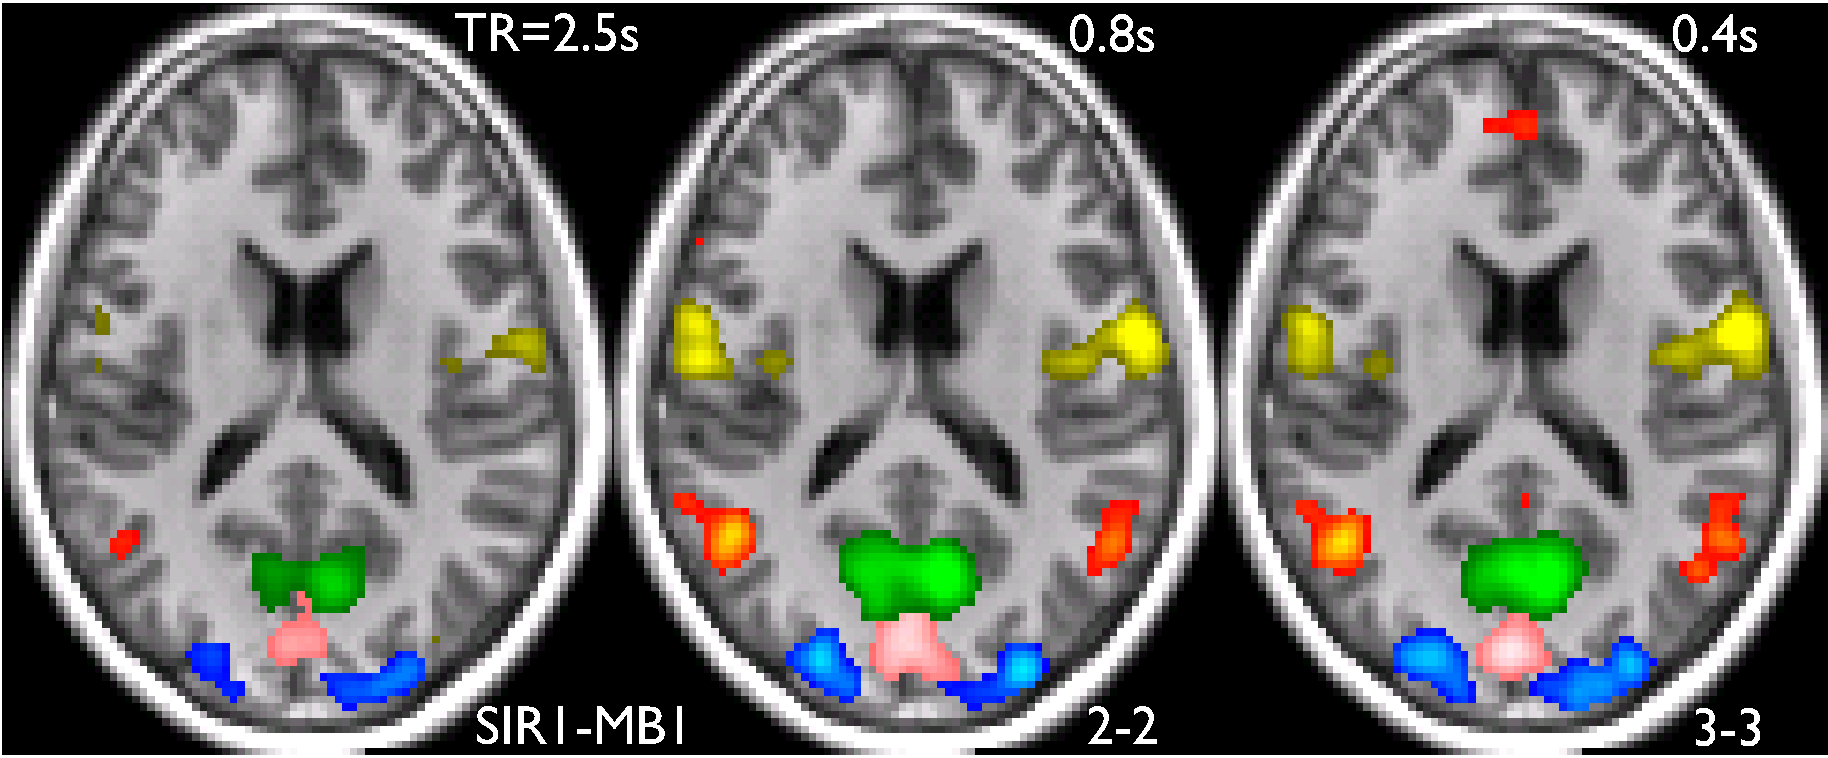

- Default Mode Network - Compounds like psilocybin reduce activity in the brain's default mode network, linked to self-referential thoughts, which may be why they help in treating conditions like depression.

- Enhanced Connectivity - Brain imaging studies show increased connectivity between different regions, which may underlie the unique experiences and therapeutic potential of psychedelics.